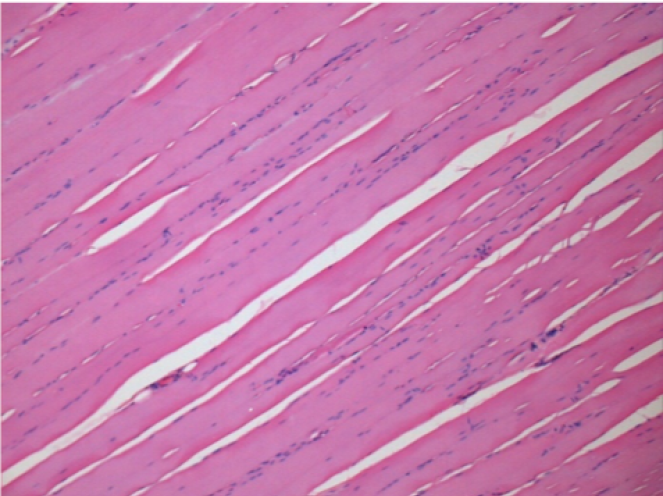

Histology

On Wistar rats

Courtesy of Lab of Pathology Department on Medicine School of Ribeirão Preto – USP

-hematoxilin-eosin

3 months (D90)after Endopeel Injection 0.1ml in the right pretibial muscle.